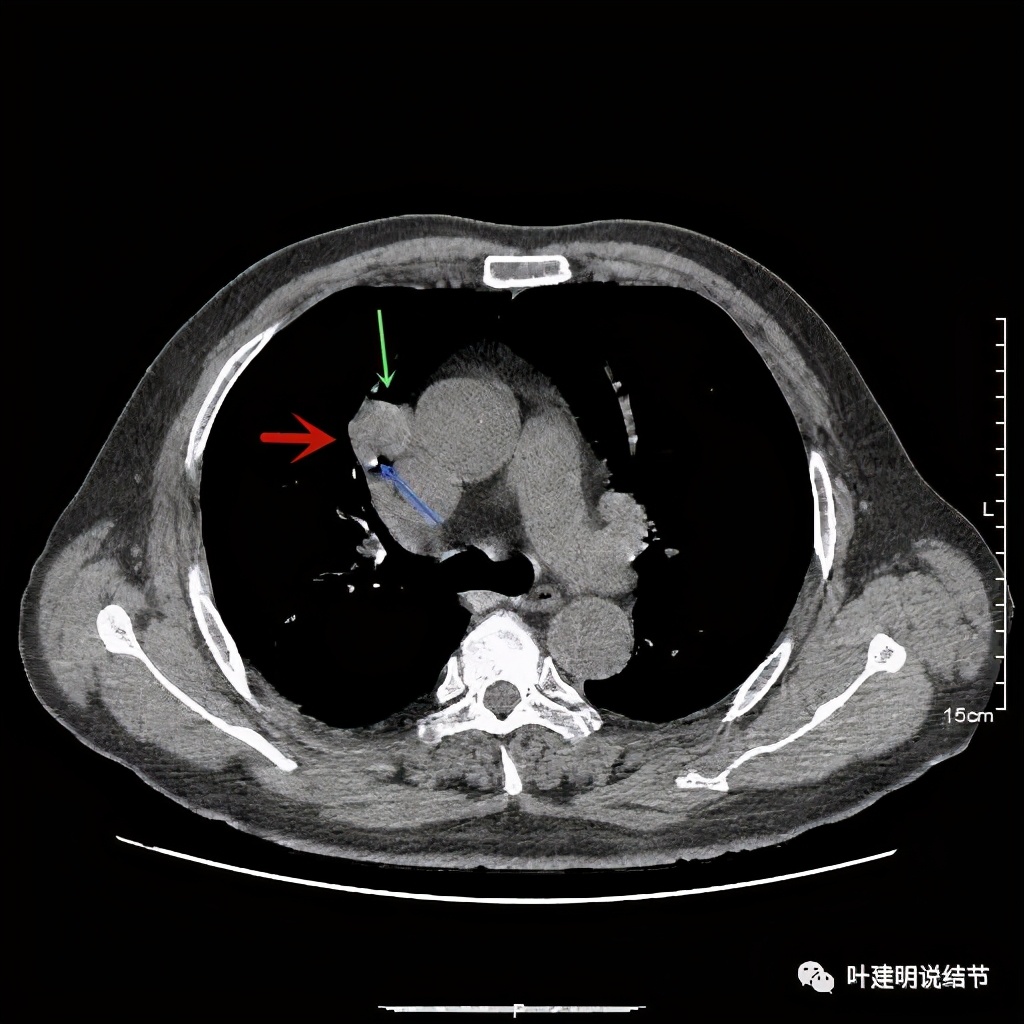

上图示病灶局部点状高密度(蓝色);边缘过于光滑(绿色)

上图示病灶密度不均,但边缘过于光滑(绿色);支气管似有截断(粉色);局部有点状钙化(蓝色)